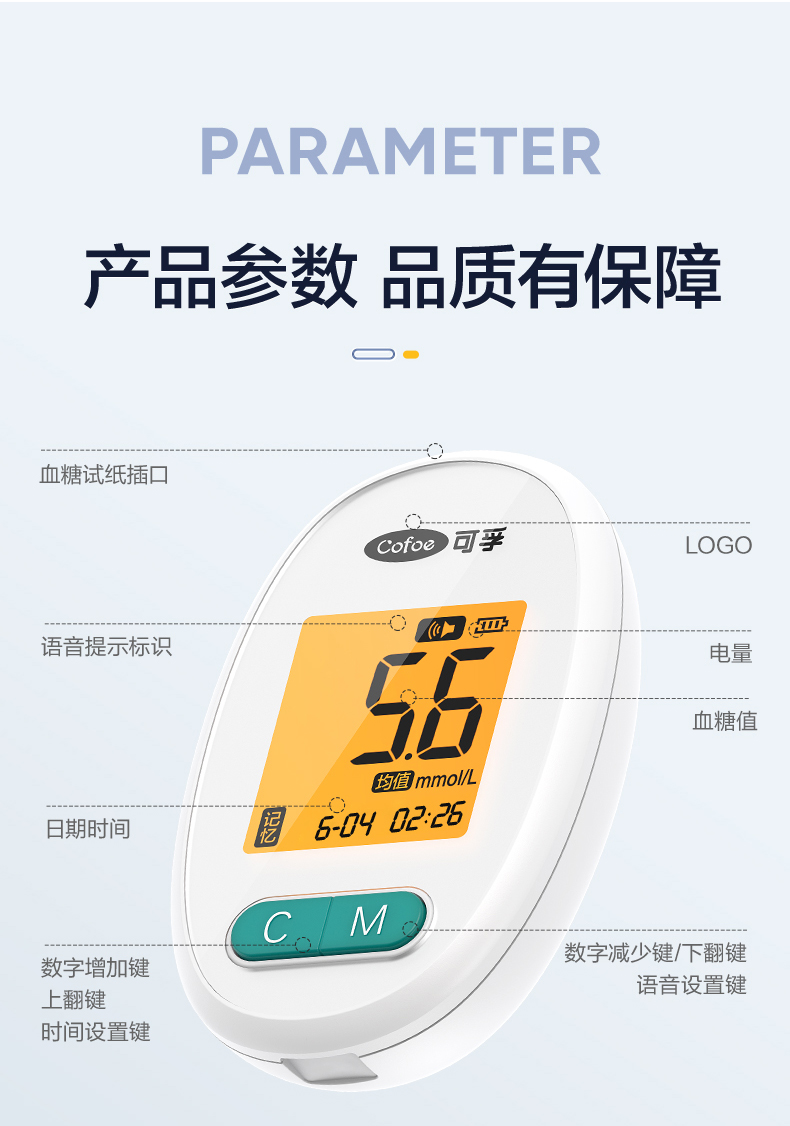

可孚新国标血糖测试仪家用测糖仪试纸官方旗舰店测血糖的仪器孕妇

Фото та опис товару